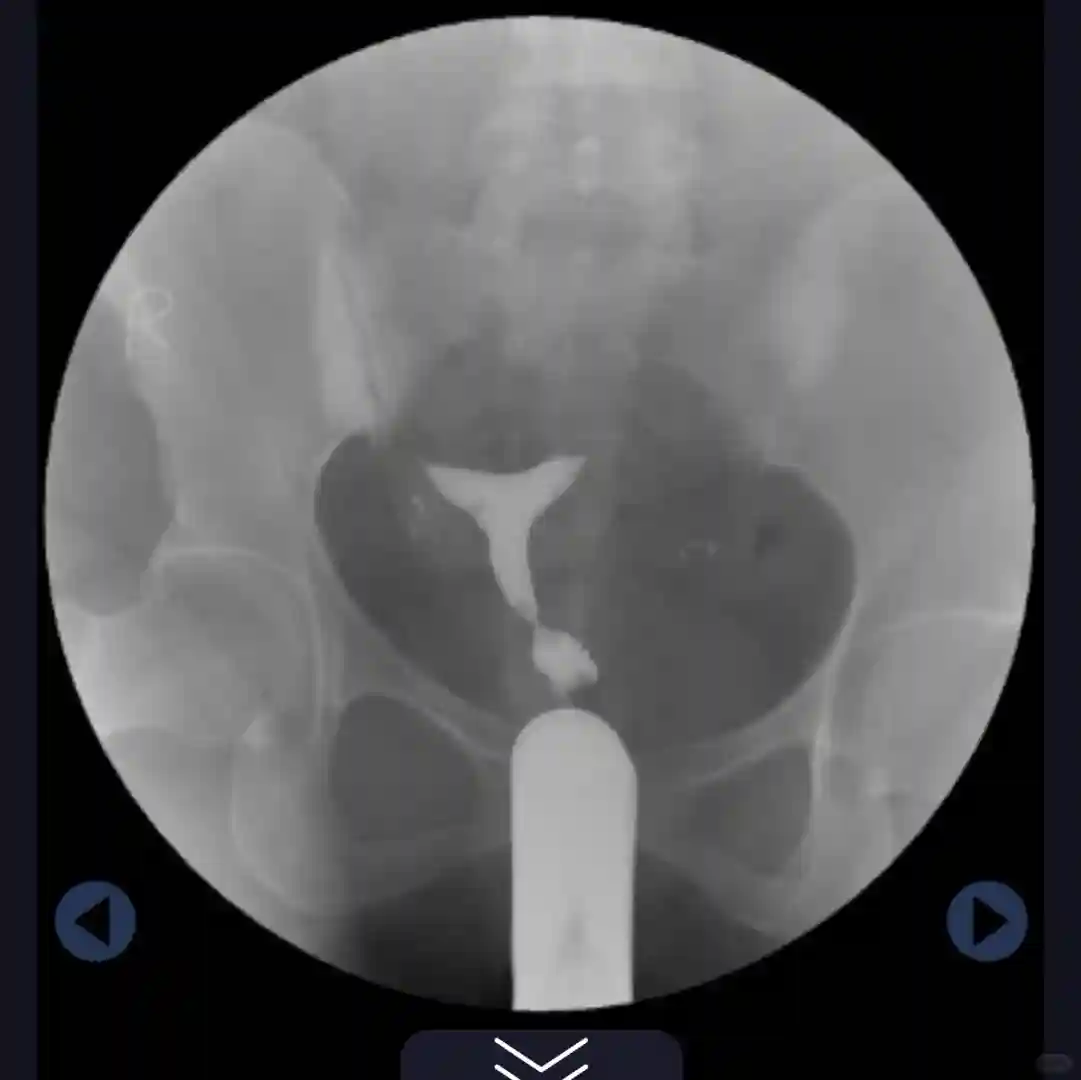

让我就不要纠结选择宫腹腔镜手术还是试管了,宫腹腔镜手术不适合我们这对夫妻,可以直接上试管了。

但是由于我过度肥胖,让我们男女方先去做个染色体检查,然后让我从现在到明年三月从160瘦到130再去找她试管,得月瘦十斤,还给我讲了减重控糖食谱,让我严格执行。

#备孕检查 #备孕日记 #试管之路 #输卵管造影 #胖多囊 #检后看报告像是看审判书